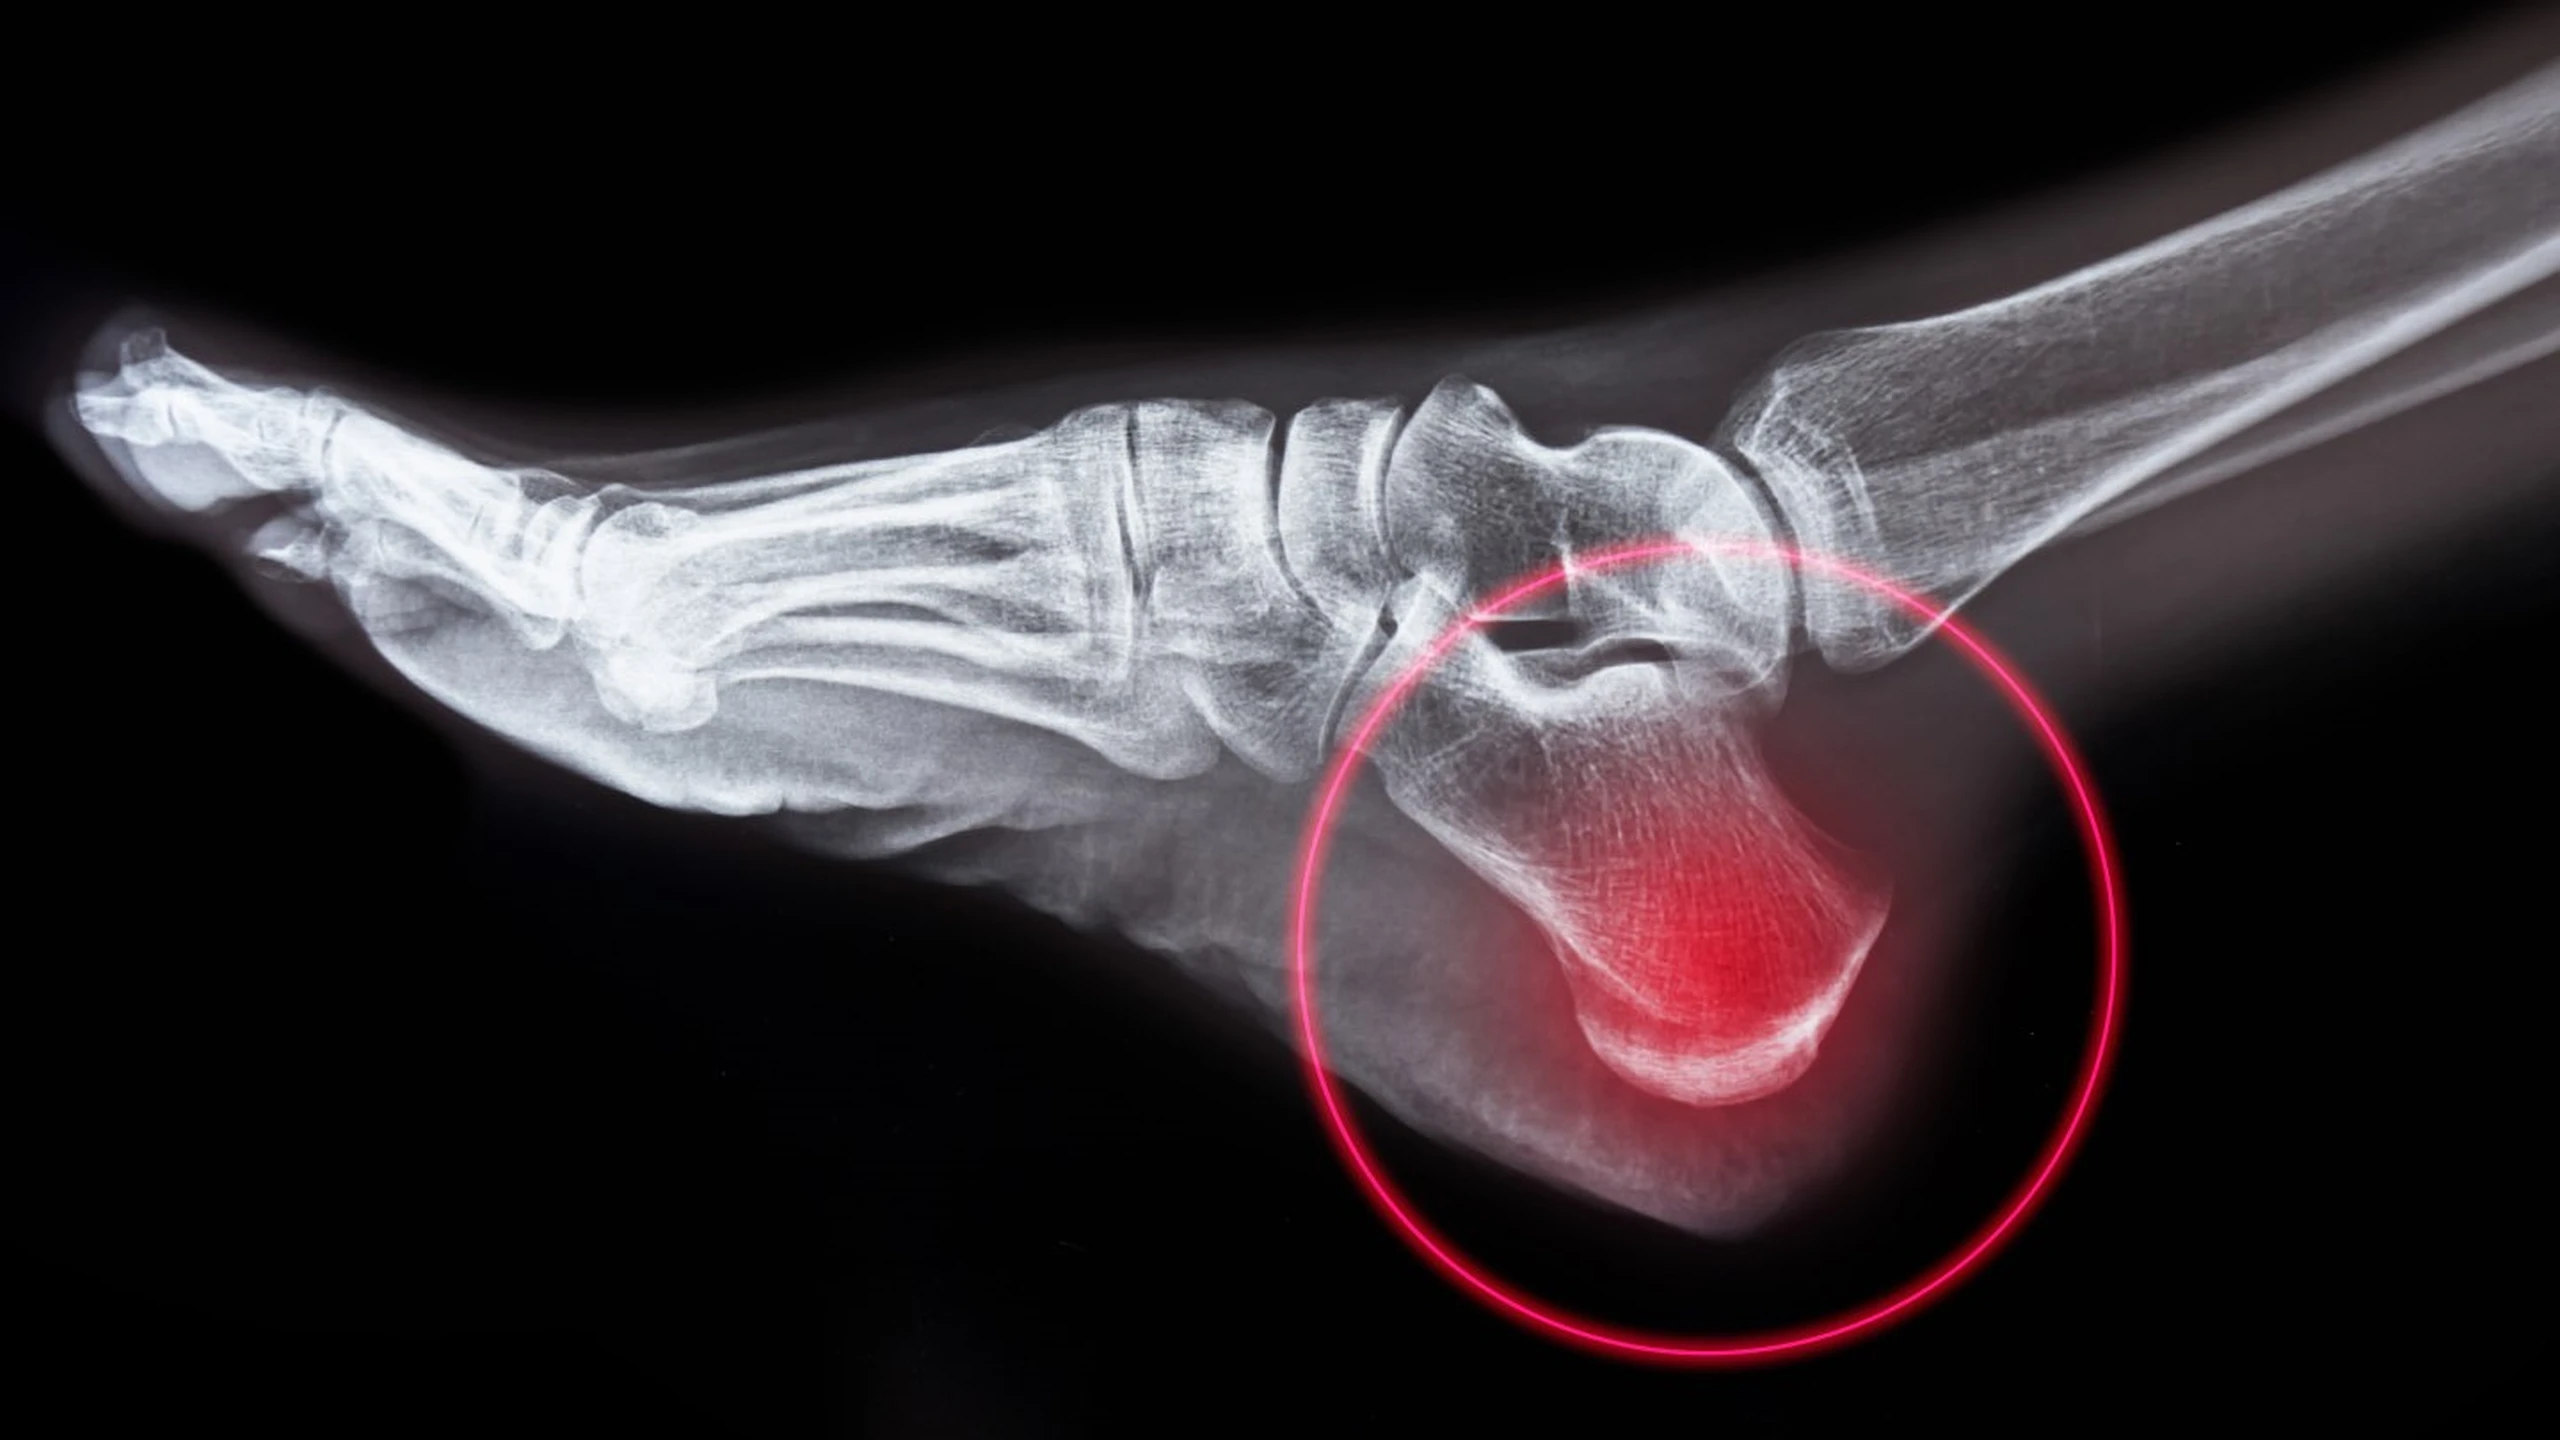

Viêm đầu xương gót hay còn gọi bệnh Sever, là một trong những nguyên nhân phổ biến nhất gây đau gót chân ở trẻ đang lớn, đặc biệt là trẻ hoạt động thể chất nhiều. Đó là tình trạng viêm của đĩa tăng trưởng ở xương gót chân. Viêm đầu xương gót là do quá trình căng thẳng lặp đi lặp lại ở gót chân. Bệnh thường xảy ra nhất trong giai đoạn tăng trưởng nhanh, khi xương, cơ, gân và các cấu trúc đang thay đổi nhanh chóng.

Viêm đầu xương gót ảnh hưởng đến phần sụn tăng trưởng ở gót chân. Vùng tăng trưởng này đóng vai trò là điểm gắn của gân Achilles (gân gót), là một dải mô chắc chắn nối cơ bắp chân với xương gót chân.

Căng thẳng lặp đi lặp lại do chạy, nhảy và các hoạt động có tác động mạnh khác có thể gây đau và viêm ở vùng tăng trưởng này của gót chân. Căng thẳng thêm từ việc kéo căng gân Achilles đôi khi có thể gây tổn thương thêm cho vùng này.

Nếu trẻ bị đau gót chân và sưng, bạn nên đưa trẻ đi khám bác sĩ. Mặc dù viêm đầu xương gót là bệnh không nghiêm trọng nhưng bác sĩ sẽ khám và có thể yêu cầu chụp X-quang để loại trừ các tình trạng khác, chẳng hạn như gãy xương. Chẩn đoán và điều trị kịp thời có thể giúp kiểm soát tình trạng này cho đến khi trẻ lớn lên.